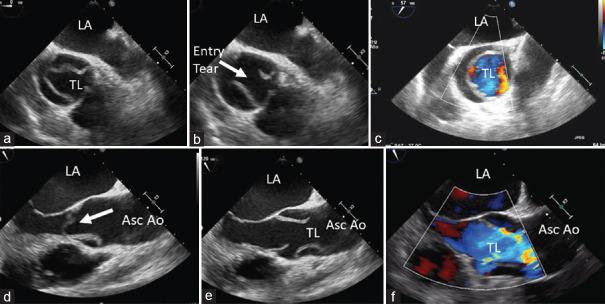

Acute aortic syndromes comprise a range of interrelated conditions including aortic dissection, intramural hematoma, penetrating atherosclerotic ulcer, and contained or not contained aortic aneurysm rupture. These syndromes are potentially life threatening; therefore, a rapid and accurate diagnosis is crucial. A new Clinical Consensus Statement on Aortic and Peripheral Vascular Disease has recently been published, and we will try to highlight the main innovations in the document.

急性主动脉综合征包括一系列相互关联的病症,包括主动脉夹层、壁内血肿、穿透性动脉粥样硬化溃疡以及有或无主动脉瘤破裂。这些综合征可能危及生命;因此,快速准确的诊断至关重要。最近发表了一份关于主动脉和外周血管疾病的新临床共识声明,我们将试图突出该文件中的主要创新之处。